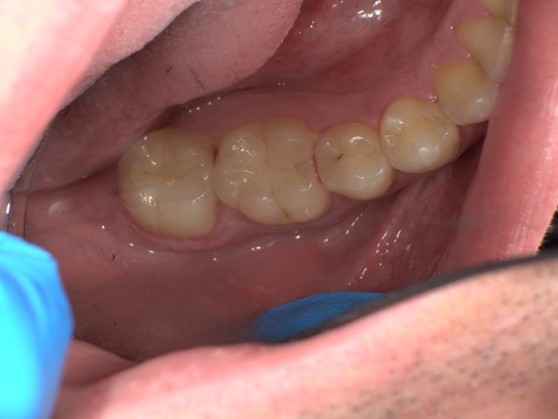

【症例No.1】左上奥歯インレー修復/50代女性

Before

After

古い詰め物を除去を行いセラミック(emax)にて修復を行いました。